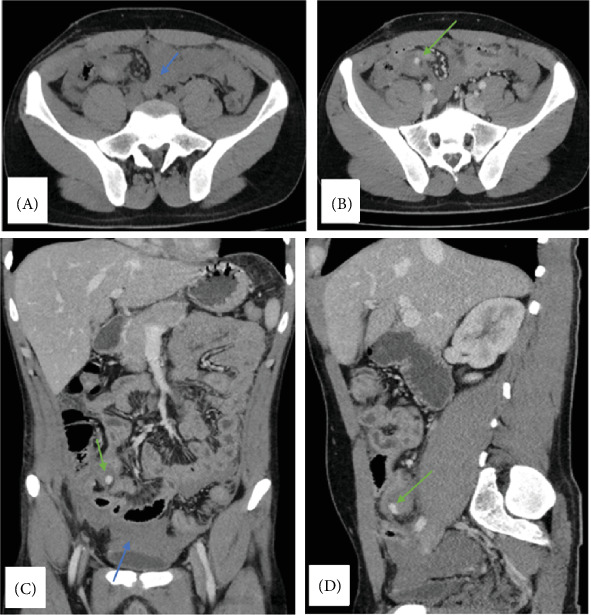

残端阑尾炎是阑尾切除术后罕见但严重的并发症,是由于阑尾切除不全而引起的。它通常与急性阑尾炎相似,但有非特异性症状,如腹痛、恶心、呕吐和发烧,使诊断具有挑战性。在这里,我们报告一个17岁的男性病例,他在接受开放性阑尾切除术后仅11天就出现了弥漫性腹痛,发烧和恶心。体格检查显示手术部位有压痛,影像学显示右下腹部有炎性改变。探查手术证实残端阑尾炎是由于保留阑尾组织,并切除。病人平静地康复了。

Stump appendicitis is a rare but serious complication following an appendectomy, resulting from incomplete removal of the appendix. It often mimics acute appendicitis with nonspecific symptoms, such as abdominal pain, nausea, vomiting, and fever, making diagnosis challenging. Here, we report the case of a 17-year-old male who presented with diffuse abdominal pain, fever, and nausea just 11 days after undergoing an open appendectomy. Physical examination revealed tenderness at the surgical site, and imaging showed inflammatory changes in the right lower quadrant. Exploratory surgery confirmed stump appendicitis due to retained appendiceal tissue, which was resected. The patient recovered uneventfully.